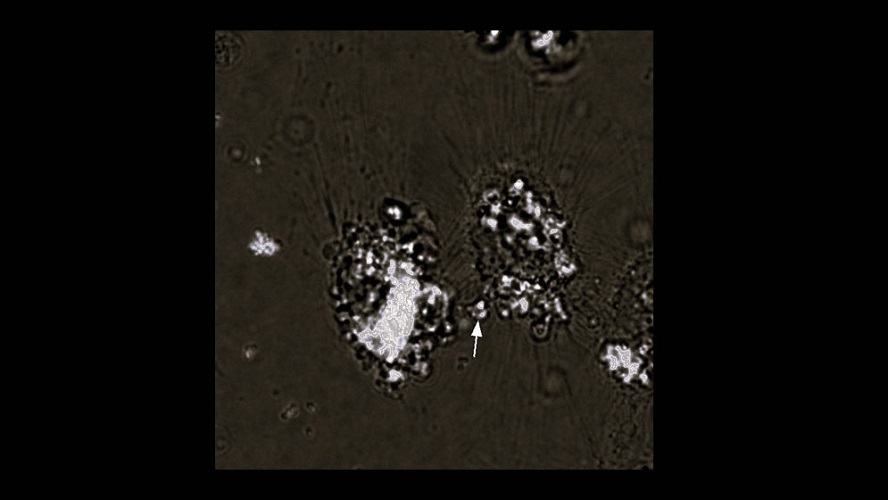

Existe mucha información acerca de cómo Brucella abortus (el patógeno de la brucelosis bovina) y en general todos los patógenos se adhieren, infectan y replican dentro de la célula, pero poco se sabía acerca de cómo salen de su interior para infectar a otras células. «En particular, en el caso de Brucella, el mecanismo de salida era totalmente desconocido. De hecho, nuestro trabajo es el primero en el que se observa a la bacteria salir de una célula infectada y además infectar una célula vecina», afirma Spera.

Los autores y autoras del estudio observaron el egreso de las bacterias en cultivos de células de ratón y humanas. Tras analizar las imágenes, descubrieron que una parte de las bacterias que egresan lo hacen recubiertas de una capa llamada «membrana eucariota» que forman a partir de materiales que «secuestran» de la propia célula infectada. «Es posible que esta membrana le brinde a la bacteria protección contra anticuerpos o antibióticos mientras infecta a una célula vecina. Estudios posteriores tendrán que confirmarlo», señala el investigador del CONICET. Y agrega: «Cuando aplicamos unos compuestos que eliminaban las membranas que recubrían a las bacterias, su capacidad para infectar a otras células disminuía de modo significativo».

Los y las especialistas del CONICET en la UNSAM también pudieron describir a nivel molecular regiones de las membranas que recubren a Brucella abortus durante el egreso de las células infectadas.